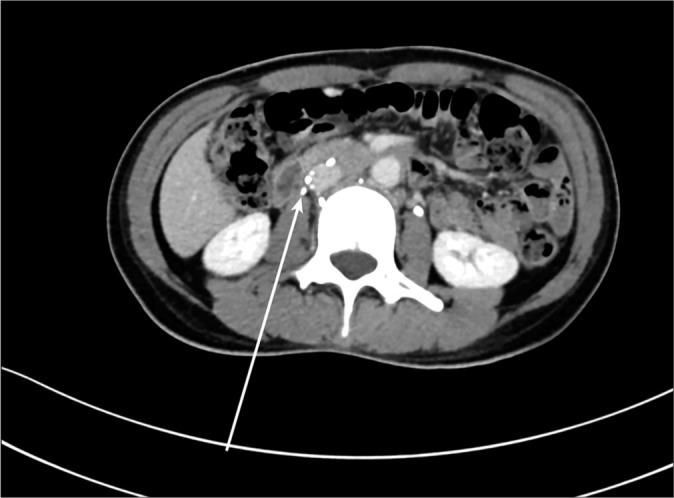

The aim of this report is to describe our experience in managing cases of difficult inferior vena cava (IVC) filter retrieval with emphasis on different advanced retrieval techniques. We report three cases of difficult IVC filter retrieval at our institution. We included three patients age ranging from 42 to 72 years. Two of the cases were presenting with the lower limb deep vein thrombosis and one of the cases had pulmonary embolism and they all had Retrievable Celect Platinum IVC filter (Cook Medical, Bloomington, Ind.) inserted preoperatively. One case was managed conservatively after failing IVC filter retrieval using standard retrieval set, meaning the filter was left in place, one was successfully removed with advanced endovascular retrieval techniques, and one failing advanced endovascular retrieval and finally had it removed with open surgery. We reviewed the risk factors contributing to difficult IVC filter retrieval and discussed the different options for managing these cases including conservative management, endovascular treatment, and open surgery for retrievable type of IVC filter which can be placed permanently. Knowledge of these options will help us better understand conditions, leading to difficult IVC retrieval on insertion, hopefully to minimize the occurrence of these cases, and to better manage cases with difficult IVC filter retrieval to decide the best option for each patient after careful consideration and multidisciplinary discussion with surgeons and patients.

本报告旨在描述我们在处理下腔静脉(IVC)滤器取出困难病例方面的经验,重点是不同的先进取出技术。我们报告了本院三例IVC滤器取出困难的病例。我们纳入了三名年龄在42岁至72岁之间的患者。其中两例患者表现为下肢深静脉血栓形成,一例患有肺栓塞,他们均在术前植入了可回收的Celect Platinum IVC滤器(库克医疗公司,印第安纳州布卢明顿)。一例在使用标准取出套件进行IVC滤器取出失败后采取了保守治疗,即滤器留在原位;一例通过先进的血管内取出技术成功取出;一例先进的血管内取出失败,最终通过开放手术取出。我们回顾了导致IVC滤器取出困难的危险因素,并讨论了处理这些病例的不同选择,包括保守治疗、血管内治疗以及对于可永久放置的可回收型IVC滤器的开放手术。了解这些选择将有助于我们更好地理解导致IVC取出困难的情况,有望尽量减少这些病例的发生,并更好地处理IVC滤器取出困难的病例,以便在与外科医生和患者进行仔细考虑和多学科讨论后为每位患者确定最佳选择。